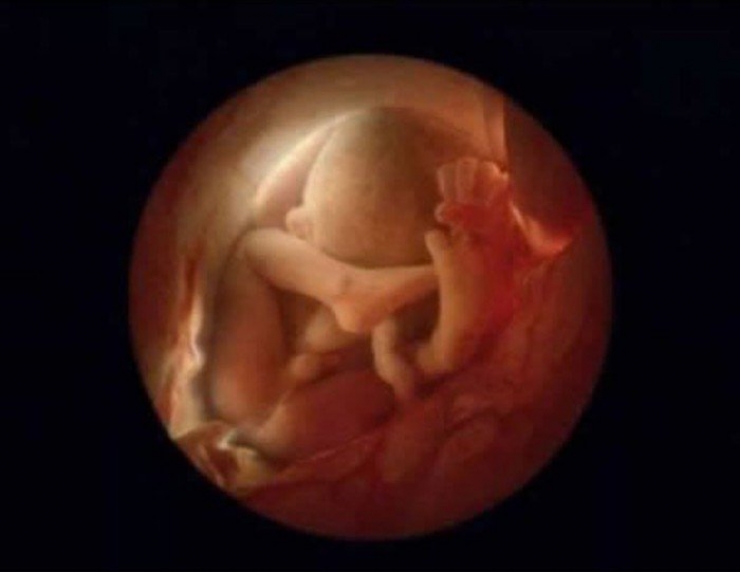

En 1965, le célèbre magazine « LIFE » (disparu aujourd’hui) utilise l’une des photos du photographe en couverture: Celle d’un d’embryon flottant littéralement dans son placenta, raccordé à sa maman via le cordon ombilical.

16: Au bout de 16 semaines (4 mois)...

21: Au bout de 24 semaines...

22: Le foetus a 6 mois!